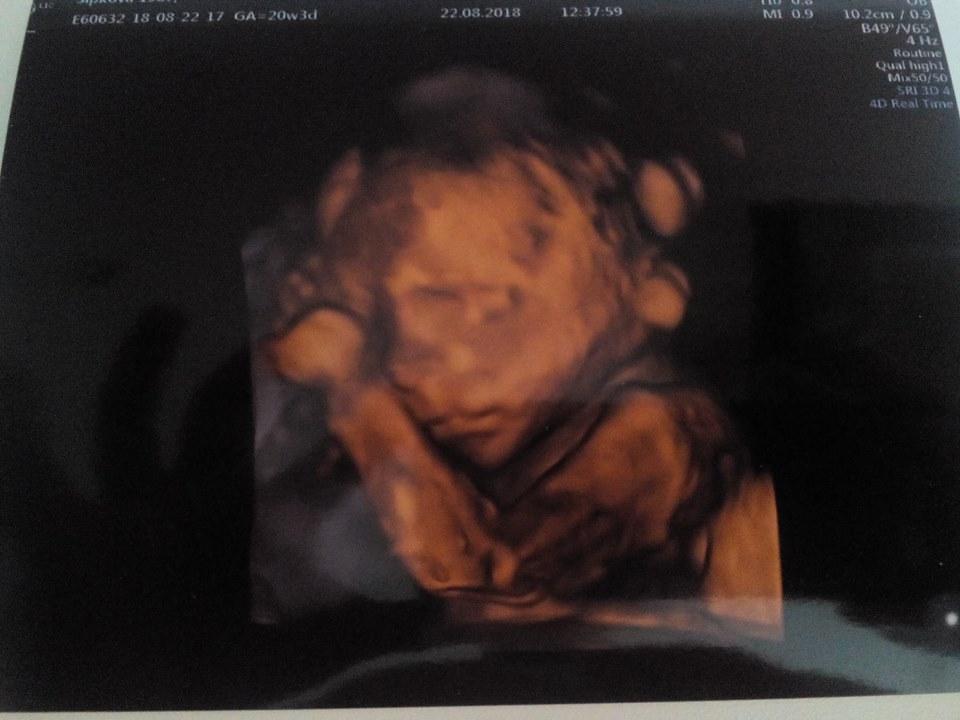

Ahojte holky, tak se Vám hlásím. Nevím proč, ale od včera jsem se sem nemohla vůbec přihlásit a hlásilo mi to, že stránka neexistuje. Jinak včerejší 2.screening byl teda docela mazec. Žádanku jsem měla s poznámkou, že jsem samoplátce. Takže jsme platili 1200kč. Byli jsme v Prenatalu na Veveří a naštěstí měli i štěstí na skvělou dr., která nám vše ukázala vysvětlila. Včera jsem byla přesně 21+0 a náš drobeček má 25cm a 430g 😀 docela mě to překvapilo a vyděsilo zároveň. Ale to nebylo to nejlepší to teprve přišlo a dozvěděli jsme se, že na 100% čekáme chlapečka a nebylo o tom pochyb bylo to vidět opravdu jasně :-/ takže šok opravdu veliký. Manžel se smál a já držela šokovaně slzy 😀 Ale jsem strašně ráda, že je vše v pořádku malý roste, tak jak má a to pohlaví vem čert 🙂 A na závěr jsme dostali fotečku a celý ultrazvuk máme natočený na DVD. Jinak hned jak dr. kontrolovalo hlavu tak se na nás miminko usmívalo, dr. z toho byla nadšená a já jsem se neubránila slzám, neskutečný zážitek a o to víc mě to těší, že to máme i zachycené na tom DVD 🙂